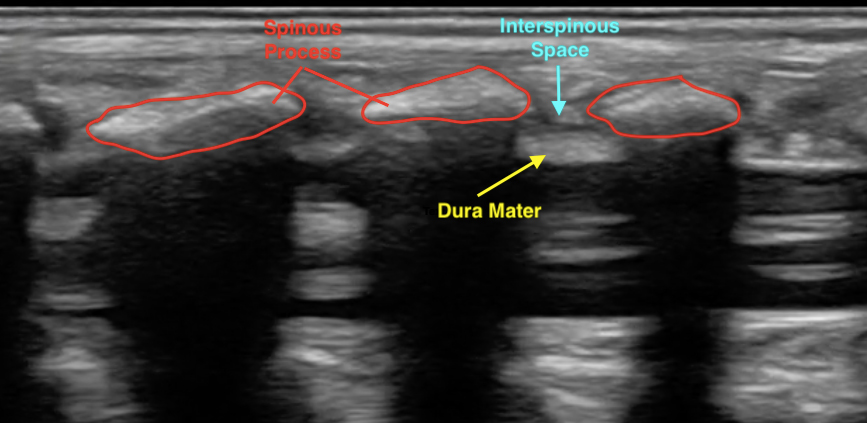

- Figure 4. Normal spinal anatomy (pediatric)